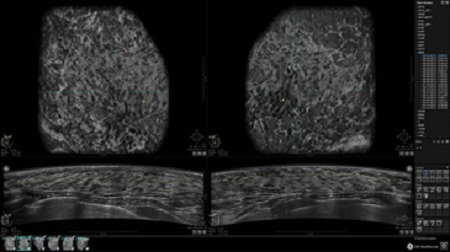

GE INVENIA ABUS – это современный УЗИ аппарат, который создан для точной и эффективной диагностики сканирования с высокой плотностью молочных желез. Выявляемость патологий раковых и предраковых стадий заболевания составляет 55%, что в конечном счете позволяет ставить врачу точные и своевременные диагнозы. Традиционные методы использования маммографии не показывают такой выявляемости, ограничиваясь лишь 3-38%.

УЗИ-аппарат GE INVENIA ABUS позволяет проводить максимально операторонезависимые процедуры, что значительно снижает риск неправильной постановки диагноза и сопутствующие издержки на обработку информации. Система готовит отчет в течение 3-х минут после сканирования, это безусловное преимущество по сравнению с обычным УЗИ сканером.

• Отображение объемных 3D ультразвуковых изображений, которые состоят из традиционных поперечных и воссозданных коронарных и сагиттальных проекций

• Возможность отображения полного 3D изображения

• Многооконный просмотр: 4 - 12 изображений

• Стандартизованная ориентация изображения: «толстый срез» в коронарной плоскости; поперечная; сагиттальная плоскость; радиальный и антирадиальный поворот изображения; просмотр исключительно области интереса

• Одновременный просмотр двух изображений для сопоставления в коронарной плоскости